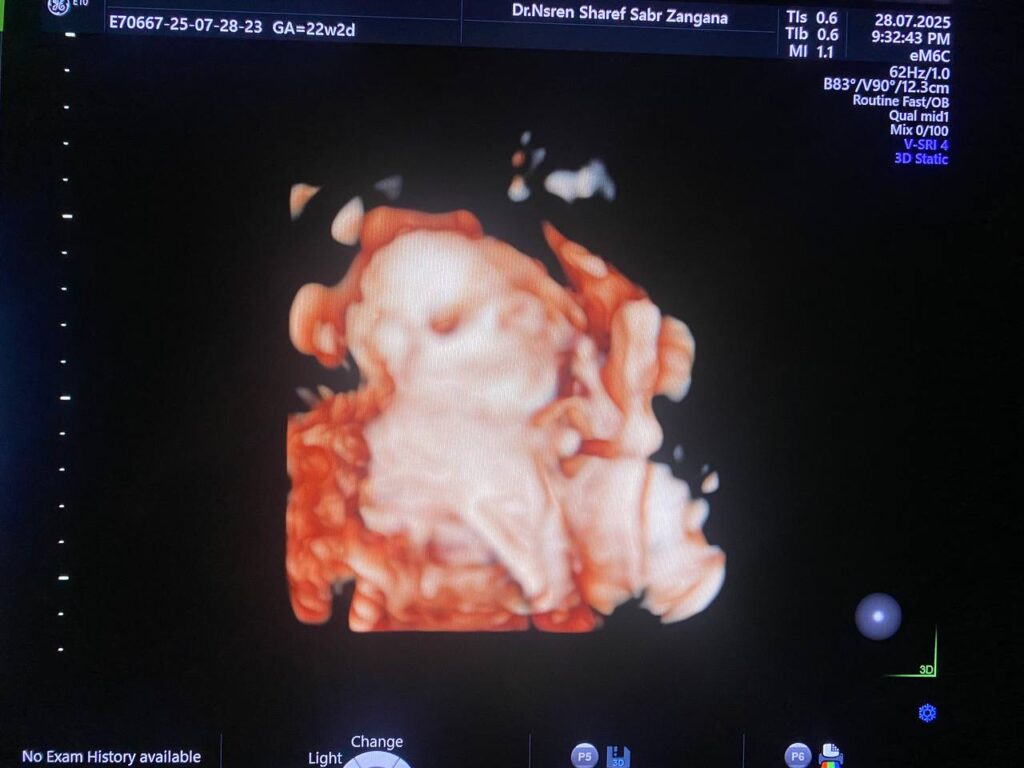

No gross congenital anomaly seen ,(right kidney size 43x25mm , left kidney size 41x25mm) , they are occupied by numerous cysts of variable sizes , the largest in the left kidney size 32x24mm, picture mostly multi cystic dysplastic kidneys ??

Mild pericardial effusion

Mildly enlarged cisternal magna magna, Mega-cisterna magna 10.6mm

Urinary bladder : empty